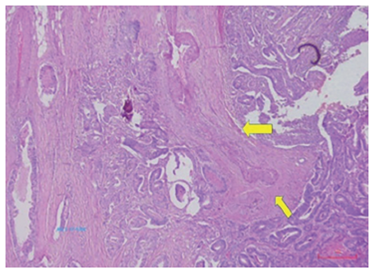

Según el estudio de histopatología de la pieza quirúrgica, se trataba de un adenocarcinoma de yeyuno, moderadamente diferenciado y polipoide, que invadía hasta la subserosa, y además, había invasión linfática y perineural. Los márgenes quirúrgicos y los ganglios linfáticos fueron negativos para tumor. Se clasificó como T3N0M0 (figuras 5, 6, 7).